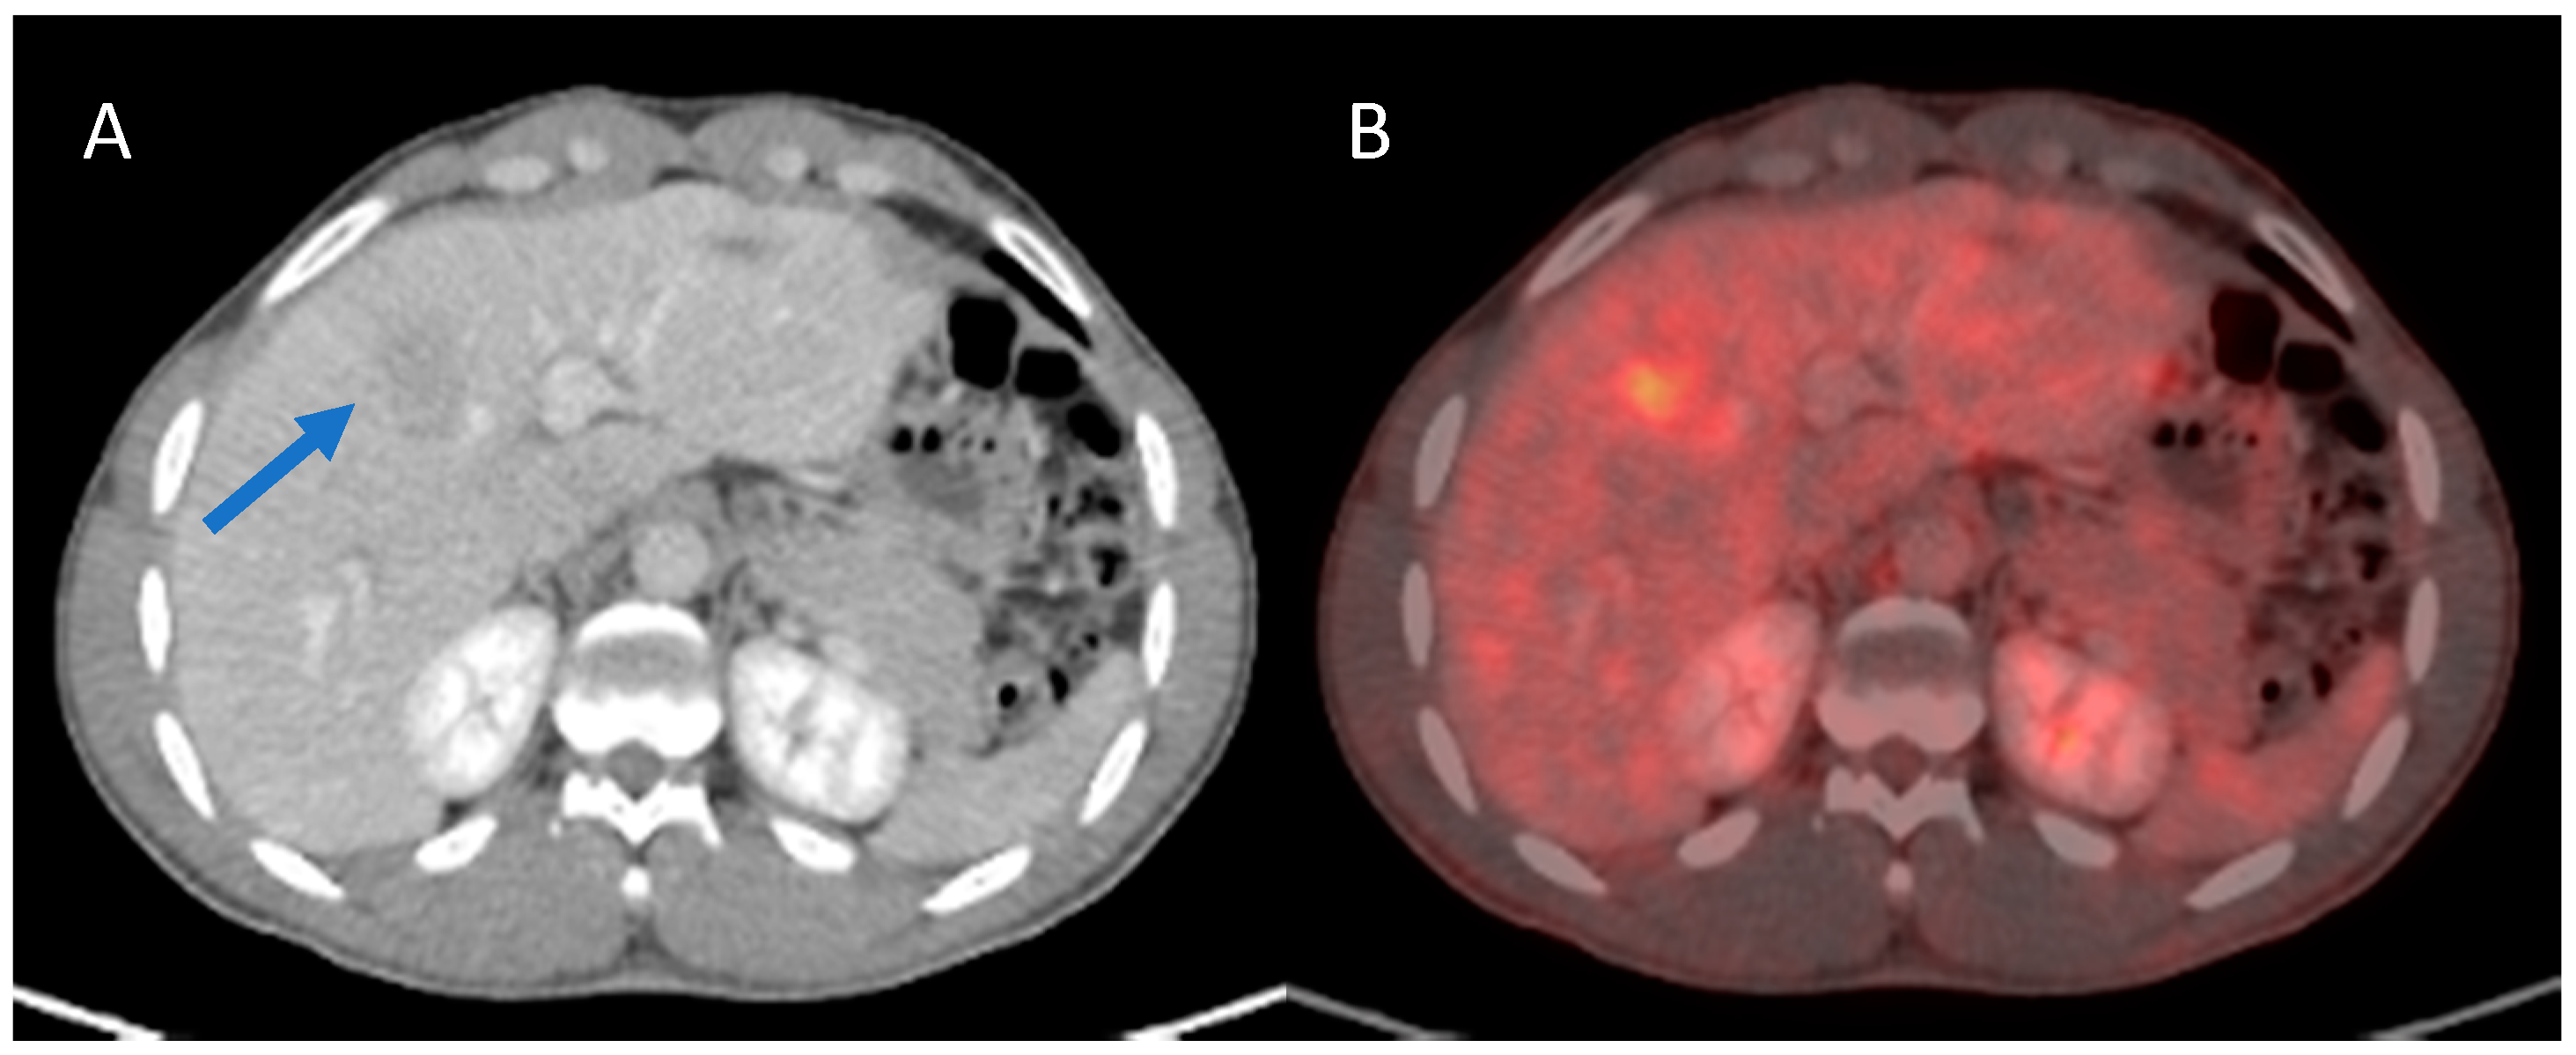

3.4. Presence of MVI and/or Poor Cellular Differentiation